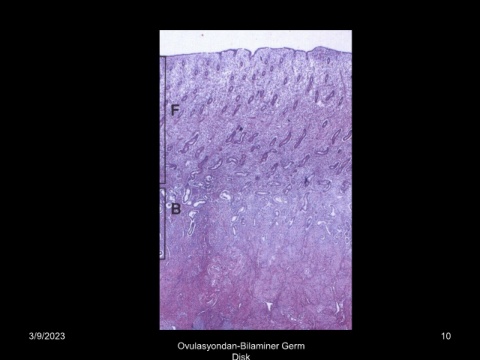

Ovulasyondan-Bilaminer Germ

Disk